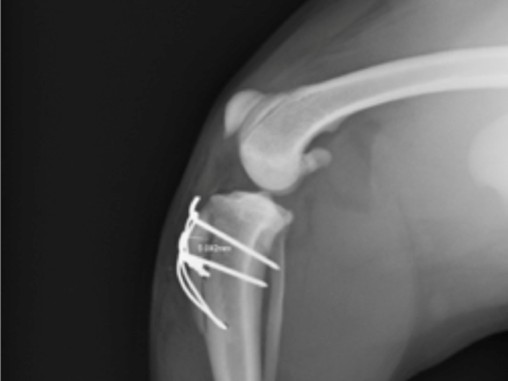

Xray image of knee after surgery